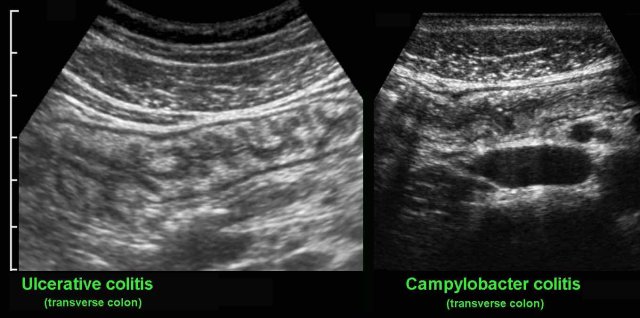

Crohn colitis vs ulcerative colitis

Finally, US may play a role in the differentiation of ulcerative colitis and Crohn’s colitis.

On clinical grounds and even with the help of endoscopy and biopsies, it can at times be difficult to differentiate Crohn’s colitis from ulcerative colitis.

In these cases, US can be of help: the demonstration of hypoechoic, transmural inflammation and the presence of non-compressible inflamed fat strongly favor Crohn’s disease.

In severe ulcerative colitis, there may be increased echogenicity of the surrounding fat (*), as here in this young pregnant lady.

This fat is rather well-compressible, and should be considered as edema associated with secondary hyperemia rather than as a sign of true transmural inflammation.

Note marked wall thickening of the transverse colon (arrowheads) in the panoramic view.